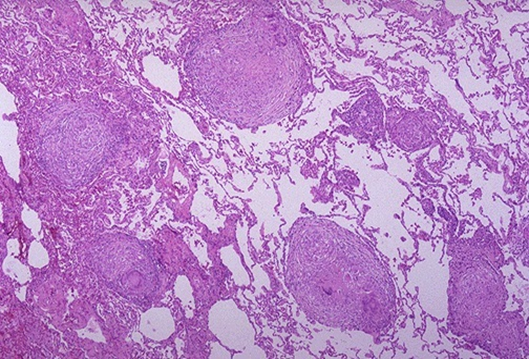

1.急性全身粟粒性结核病(acute systemic miliary tuberculosis)

原因:结核杆菌在短时间内一次或反复多次大量侵入肺静脉分支,经左心至体循环,播散到全身各器官如肺、肝、脾和脑膜等处引起。

多见于原发性肺结核病恶化进展,又可见于其他类型的结核病播散,甚至见于死产的胎儿。

肉眼:各器官内均匀密布大小—致,灰白色,圆形,境界清楚的小结节。

镜下:主要为增生性病变,偶尔出现渗出、坏死为主的病变。

临床:病情凶险,有高热衰竭、烦躁不安等中毒症状。

X线:两肺有散在分布、密度均匀、粟粒大小细点状阴影。